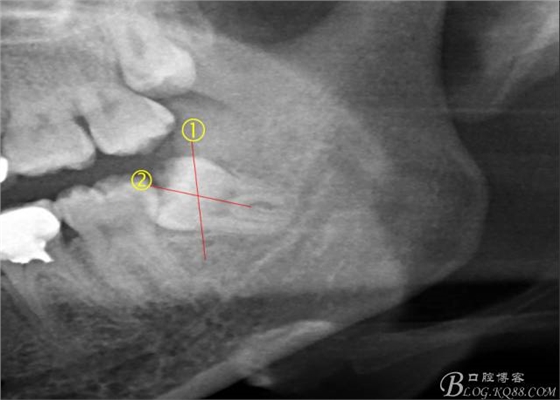

術(shù)前分析:智齒分牙的方法不少,但個人感覺都與這十字分牙法差不多,大多數(shù)阻生齒的分牙都在此基礎上進行改進。